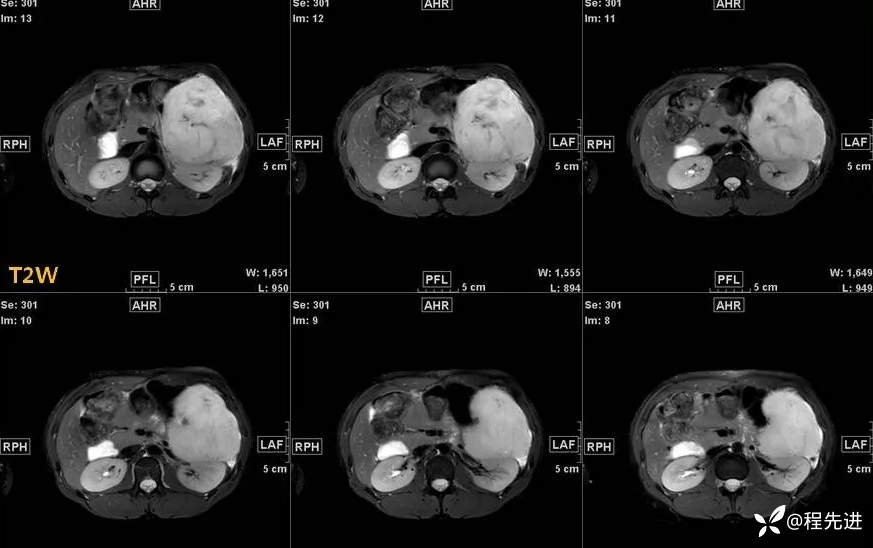

影像检查:

T1: